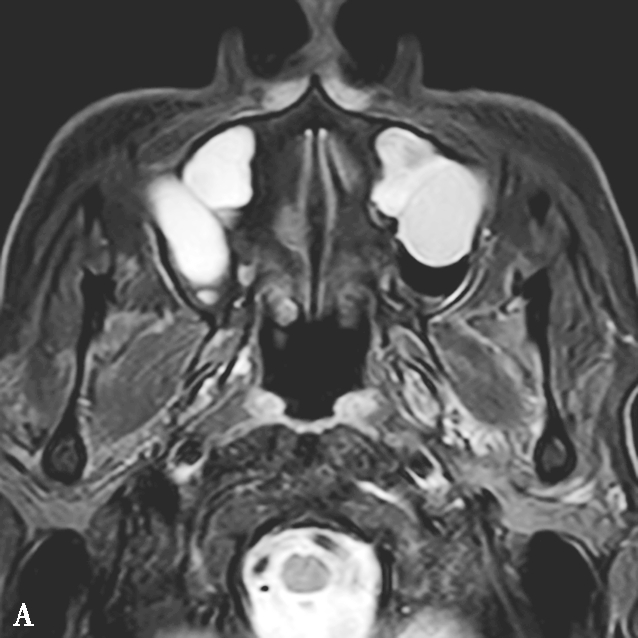

图1-3-21 真菌球

A~C.横断面CT骨窗、横断面软组织窗、冠状面CT骨窗,A、C示左侧上颌窦内充填软组织密度影,伴中央多发条状、云絮状高密度影,上颌窦窦口扩大,窦壁骨质增生硬化、肥厚;B示窦腔实变,中央高密度影显示更清楚;D~F.MRI横断面T 1 WI、T 2 WI及增强T 1 WI,示左侧上颌窦内软组织影,T 1 WI呈等、高信号,T 2 WI呈等、高信号,窦口区病变T 1 WI呈不规则形等、稍高信号,T 2 WI呈极低信号,增强扫描后窦口区病变无强化,周边黏膜呈线样强化

4.CT表现

①平扫表现:受累鼻窦窦腔不均匀实变,病变中央可见点、细条或云絮状高密度影,融合成团块状,密度高于软组织但低于骨质,平均CT值约140HU,由真菌菌丝中的钙盐、铁和镁等重金属形成。窦壁骨质增生伴骨质破坏,骨质破坏多见于近上颌窦自然开口处(图1-3-21A~C)。②增强扫描表现:边缘黏膜明显强化。

5.MRI表现

①T 1 WI表现:真菌菌丝呈低信号或等信号;外周黏膜炎症为中等信号。②T 2 WI表现:呈极低信号,甚至无信号;外周黏膜呈高信号。③增强扫描表现:真菌菌丝无强化,边缘黏膜明显强化(图1-3-21D~F)。